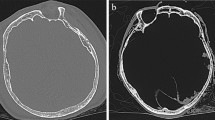

The sample included 414 adult individuals from the Croatian population, with an equal proportion of males and females (median age 64; range 18–95). The multi-slice computed tomography (MSCT) images were retrospectively collected from university hospital centers’ diagnostic and interventional radiology departments in Split (n = 219) and Zagreb (n = 196), the two greatest Croatian towns from different regions (To avoid repeating phrases like crania imaged in Split or Zagreb hospitals, we will refer to them as Split and Zagreb crania in further text).

The images were acquired using MSCT device Definition Edge and Sensation AS 128 (Siemens AG Medical Solutions, Erlangen, Germany). We included head region images with a slice thickness of ≤ 1 mm that showed no visible pathological and traumatic changes or significant asymmetries. We used the original slice thickness and soft-tissue convolution kernel for image reconstruction.

DICOM files were loaded into Stratovan Checkpoint Software Version 2020.10.13.0859 (Stratovan Corporation, Davis, CA) and viewed in 2D (axial, sagittal, and coronal plane) and 3D using semi-transparent 3D volume rendering. Following the previously described protocol and workflow54, crania were aligned, and 47 landmarks were placed in specific order according to a template (as detailed in the Supplementary Table 2). These landmarks correspond to standard measurements outlined in the Data Collection Procedures for Forensic Skeletal Material 2.055 and were stored as .nts files.